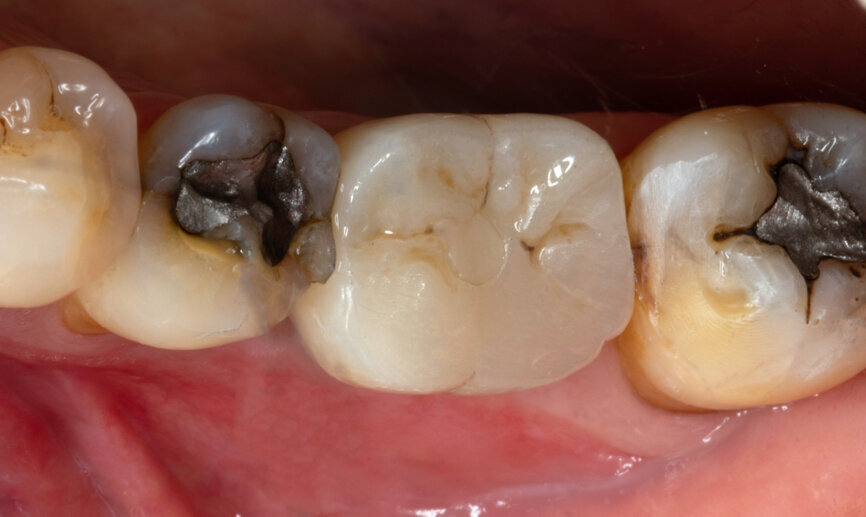

Fig. 1: Intra-oral occlusal view.

After careful assessment of the patient’s anatomical condition through a panoramic radiograph and CBCT scan (Figs. 1–3), it was possible to verify ideal interradicular bone availability, allowing the following treatment plan:

A 68-year-old male patient, a non-smoker, presented with controlled Type 2 diabetes. He had undergone previous dental implant treatments with positive results in the past. The patient presented to the office with tooth #36 in a non-restorable condition with indication for extraction. He requested a dental implant as the treatment choice.